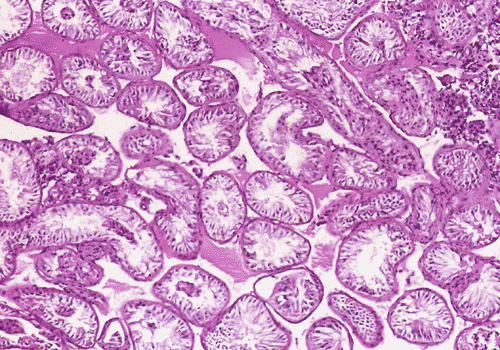

On low-magnification (Panel A), the diameter of the seminiferous tubules appeared to be slightly decreased. There is, however, no thickening of the basement membranes, interstitial fibrosis, or inflammation. On medium and high- magnification (Panel B and C),the seminiferous tubules are lined by columnar Sertoli cells which have triangular to ovoid nuclei, pale-staining chromatin, and prominent central nucleoli. The salient feature is the total lack of spermatogenesis (Panel C). The interstitium contains a few scattered clusters of Leydig cells without definitive evidence of hyperplasia (Panel D).

DIAGNOSIS: Sertoli cell-only syndrome (germinal cell aplasia), mature (adult) variant.

In the mature variant, the seminiferous tubules are lined by mature-appearing columnar Sertoli cells, some which have roughly triangular (so-called tripartite) nuclei and/or vacuolated cytoplasm. Seminiferous tubular diameters are smaller than in normal adult testes, but larger than in immature SCOS; tubular lumens are open. The putative pathogenesis is failure of migration of germ cells from the primitive yolk sac to the gonadal ridge. In spite of this, the Sertoli cells, under normal hormonal regulation, develop relatively normally. Some patients with mature SCOS have a history of viral orchitis; many cases are idiopathic.